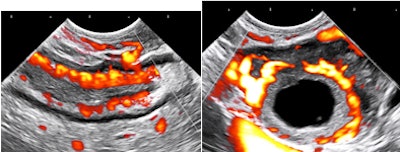

Let's have a look at some selected images from a recent study of a 30-year-old woman with uncertain dates and a positive pregnancy test:

![]() |

| All images courtesy of Dr. Jason Birnholz. |

There is a intrauterine pregnancy with a (right) corpus luteum with an intact vascular margin. A regular heart rate of 122 beats per minute implies a 6.0-week stage. The Doppler pattern has separate filling and ejection phases. The decidual boundary is thick and well implanted. But there was another unexpected finding when looking at the left ovary: